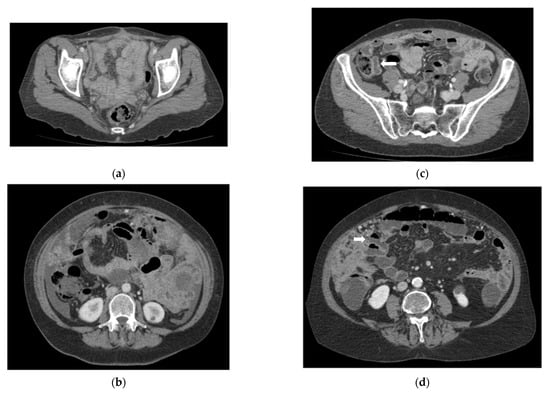

:1. Introduction

2.3. Pre-Surgical Radiological Assessment: CT Study Protocols

2.3.1. Routine CT (rCT)

2.3.2. CT Enterography (CTE)